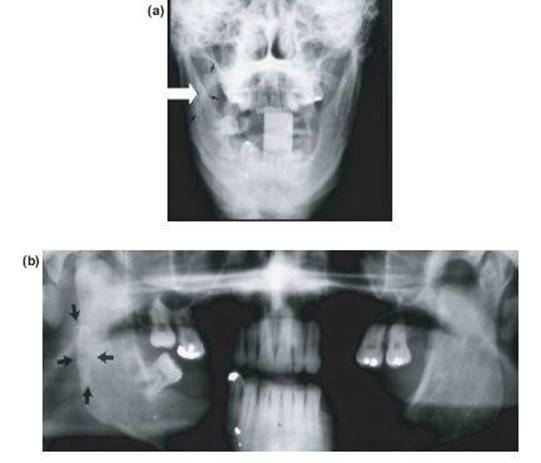

Figure 13.15 (a) and (b) Gradual postoperative onset of impaired opening due to fibrodysplasia ossificans of the medial pterygoid muscle. Treated with 3 months bisphosphonate and stretching.

• Postoperative fibrodysplasia ossificans in the medial pterygoid and masseter can occur and will also require bisphosphonates and stretching exercises for 2-3 months (Figures 13.15a and 13.15b).